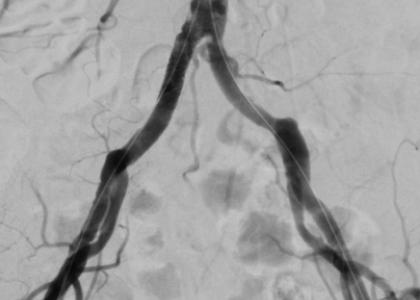

Arterielle Durchblutungsstörungen

Schaufensterkrankheit, Verengung der Hirnschlagader und akute Gerinnsel der Beinarterien. Rechtzeitig erkannt, lassen sich arterielle Durchblutungsstörungen gut behandeln.